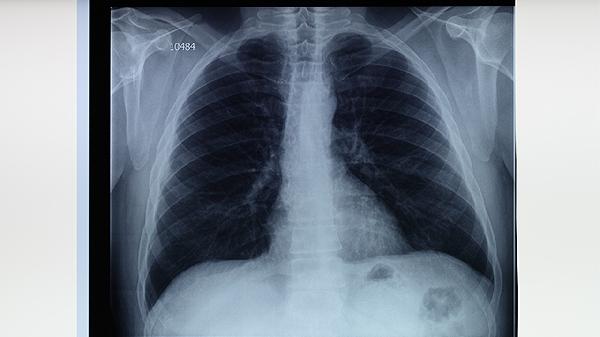

出现持续咳嗽、低热、盗汗等疑似结核症状时,应及时进行痰涂片检查与胸部影像学诊断。确诊前不建议自行使用止咳药物,以免干扰病情判断。治疗期间应保持室内通风,佩戴口罩防止飞沫传播,注意补充优质蛋白和维生素A/D增强免疫力,避免辛辣食物刺激呼吸道。